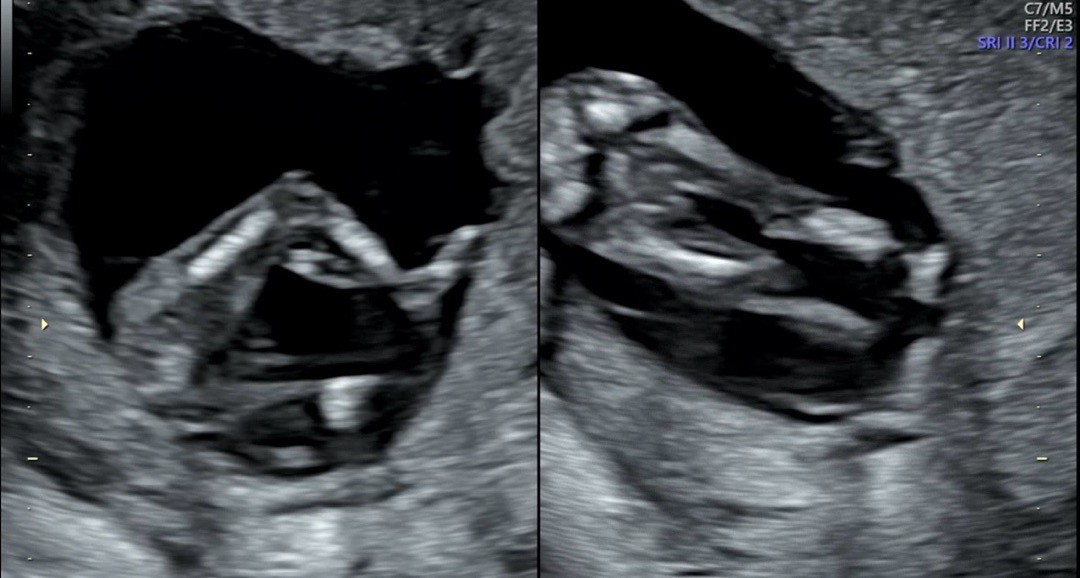

12주6일차에 1차 기형아 검사했어요!! 한달 후에나 성별 알수 있을텐데 참다참다 너무 궁금해서 올려봐요 혹시 근처 병원가서 초음파 보면 성별 알수 있을까요?(현재14주5일차입니다)아그리고!!태몽꿈은 두개 꿨는데 1개는 엄~청큰 물고기꿈 꿨구요 2번째는 앵두,자두나무 보고 딸기밭에서 딸기따먹는 꿈꿨어요!! 태몽꿈 여러개 꿀수도 있나요? 아직 주차가 일러서 보일지 모르겠지만 혹시나 선배님들이 봐주시지 않을까 싶어서 올려봐요 🙇♀️🫶🏻

12주차때는 아들도 딸도 생식기가 다 튀어나와있어서 아래 초음파보다는 각도법으로 추측하는 정도에요! 빠르면 15주차 즈음에 아래 사진으로 볼 수 있어요!